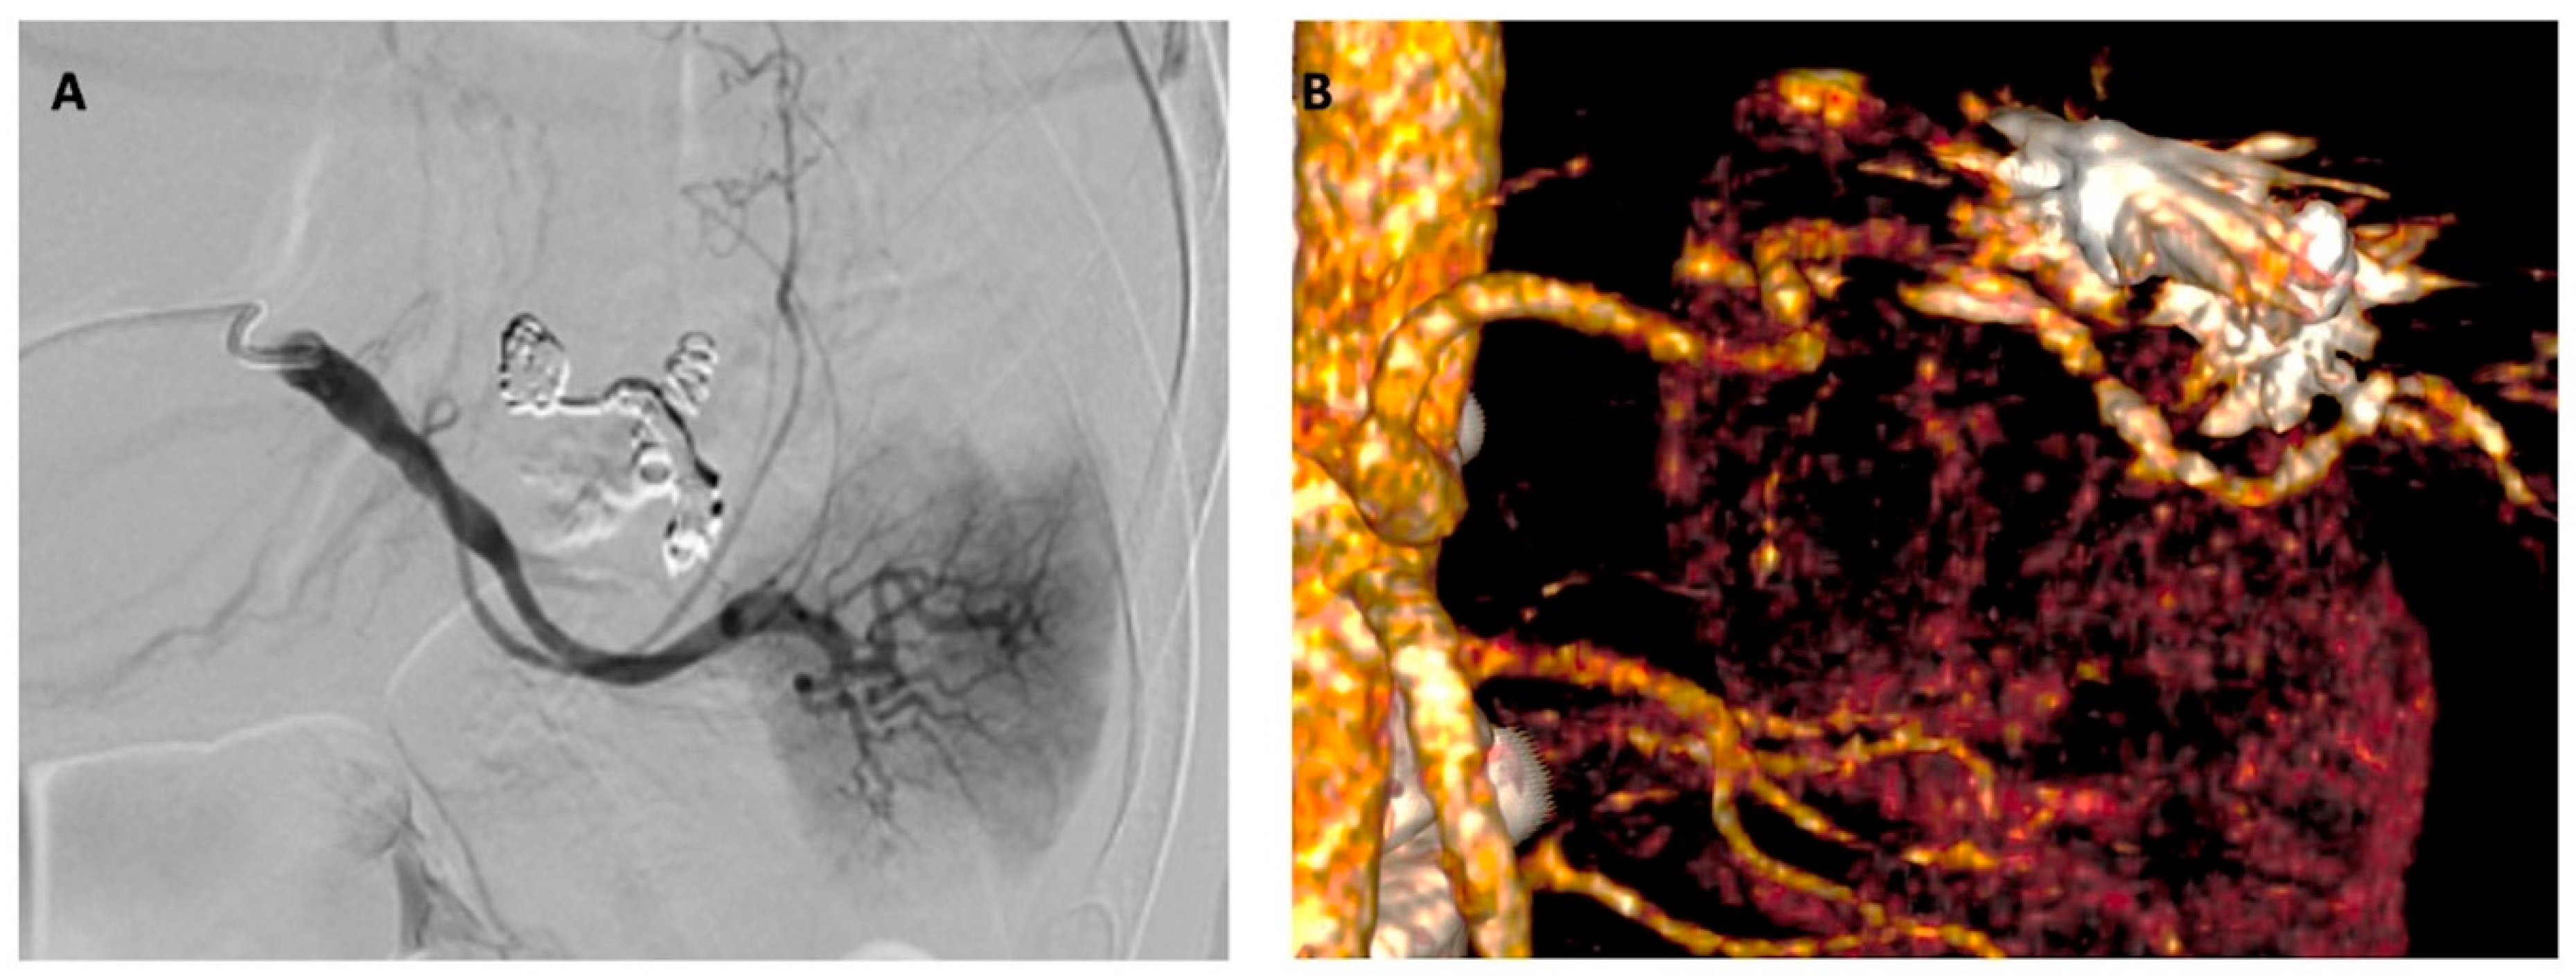

2. Detailed Case Description